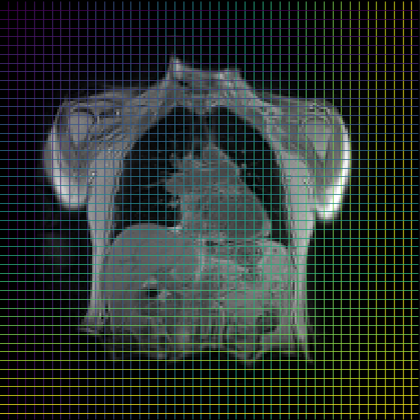

Finally, in Figure 2, we present the deformed image produced by the proposed method on coronal view for a single patient in the two different moments of the respiratory cyrcle. The grids were superimposed on the images, indicating the displacements calculated by the network. The last column shows the difference between the reference and deformed image. One can observe that the majority of the errors occur on the boundaries, as the network fails to capture large local displacements.